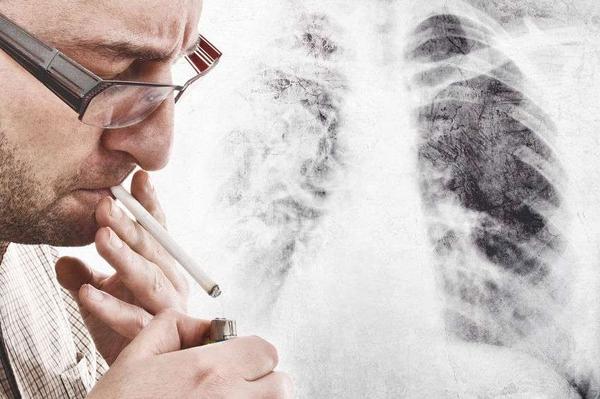

之所以会如此,与我国男性的吸烟人数庞大、工作性质、遗传基因等多个方面都有关联,这其中最危险的因素就是“吸烟”。

长期吸烟、接触烟草的年龄越小,未来出现肺癌的几率也就会越大。长期吸烟者患肺癌的几率,甚至是不吸烟人群的10-20倍。

而在我国,16岁以上的男性中,有超过了60%都有长期吸烟史,烟民的数量庞大,为我国男性肺癌病发率打下了基础。